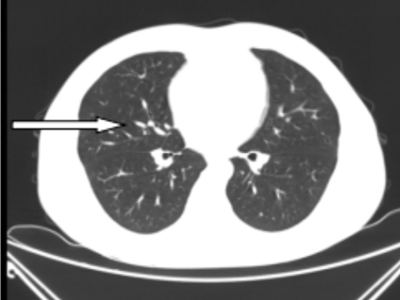

41岁的彭先生,2022年3月份出现咳嗽咳痰,多家医院治疗效果不佳,外院查胸部CT提示肺部占位及大量胸水,且外周血白细胞明显升高及颈部多发的淋巴结肿大。4月初疑诊结核收入我院结核科,入院后发现浅表淋巴结进行性增大,经血液科会诊,考虑淋巴瘤并骨髓侵犯。患者转入血液内科后,行骨髓涂片提示有77%肿瘤细胞,同时请耳鼻喉科行颈部淋巴结切除病检,最终确诊为低级别滤泡性淋巴瘤并肺部、骨髓侵犯(IV期,EZH2基因突变阴性)。4月27日根据最新的滤泡性淋巴瘤诊治指南(NCCN指南及CSCO指南),选用GB方案(奥妥珠单抗联合苯达莫司汀)化疗。第一周期化疗后,彭先生状态良好。5月26日复查肺部CT,肺部占位、胸水及淋巴结明显缩小。咳嗽及气促也完全消失。目前,患者仍在血液内科接受后续治疗。

图二:5月26日第一次化疗后肺部CT,箭头所指的肺实变已消失